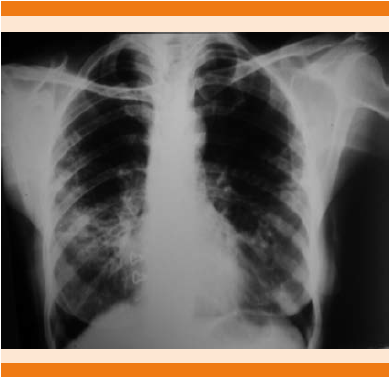

Inició en junio de 2008 con tos productiva, esputo blanquecino, acompañado de hemoptoicos escasos, en accesos, no disneizante ni emetizante, sin fiebre, sin pérdida de peso, se diagnosticó de manera inicial como bronquitis aguda, por lo que se administró tratamiento antibiótico con betalactámicos, sin remisión de los síntomas; al considerar la exposición a humo de biomasa se diagnosticó clínicamente enfermedad pulmonar obstructiva crónica, se inició tratamiento con agonistas beta 2 adrenérgicos de acción prolongada con esteroide inhalado, salmeterol 50 µg/fluticasona 100 µg, dos inhalaciones cada 12 horas y anticolinérgicos de acción prolongada, tiotropio cápsulas de 18 µg, una inhalación al día. Se mantuvo en control durante tres años, sin ningún episodio de exacerbación que requiriera hospitalización pero con persistencia de síndrome tusígeno crónico, reinició con hemoptoicos en 2011, que eran esporádicos con exacerbación relacionada con cambios de clima, por lo que se solicitaron baciloscopias en esputo seriadas que resultaron positivas ++/+++ y radiografía de tórax (Figura 1); se estableció diagnóstico de tuberculosis pulmonar, se inició tratamiento de seis meses con Dotbal® (rifampicina 150 mg/isoniazida 75 mg/pirazinamida 400 mg/etambutol 300 mg) en fase intensiva y de sostén. Por persistencia de tos, pérdida de peso y baciloscopias positivas +++ en 2012 se dio tratamiento durante dos años, considerando recaída de tuberculosis pulmonar, con baciloscopias positivas + y ++, en algunas ocasiones negativas, con reajustes intermitentes del esquema antituberculoso, se valoró por los servicios de Neumología e Infectología, se solicitó tomografía torácica (Figura 2) y cultivo de expectoración, como lo marcan los lineamientos nacionales, gestionado por el Laboratorio Estatal de Salud Pública de Tamaulipas y el Instituto de Diagnóstico y Referencia Epidemiológicos (InDRE), con desarrollo de Mycobacterium abscessus en dos muestras separadas y que, aunado al cuadro clínico, se estableció el diagnóstico de micobacteriosis pulmonar secundaria a Mycobacterium abscessus, por lo que se decidió inicio de tratamiento en noviembre de 2014 con amikacina 500 mg intramuscular c/24 horas durante dos meses más claritromicina 500 mg c/12 horas de manera indefinida, por no ser apta para resección de la lesión por afección bilateral no se envió a valoración de cirugía cardiotorácica.

Figura 1 Radiografía de tórax con radioopacidades retículo-nodulares bilaterales de predominio derecho en la región perihiliar e hiliar.